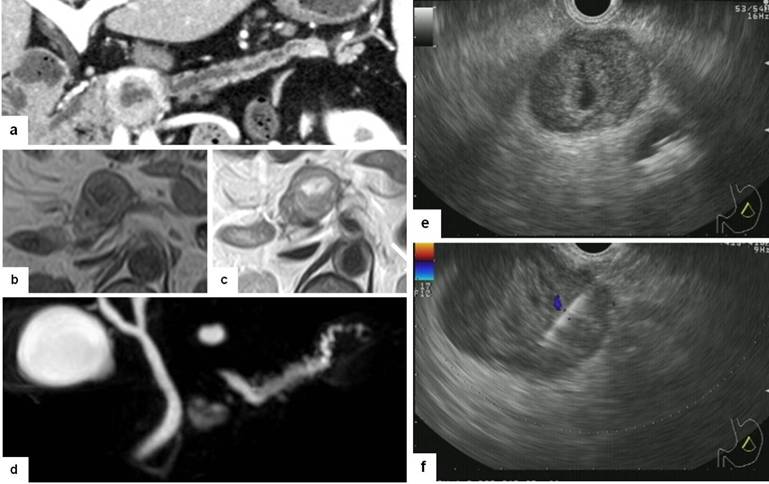

A 62-year-old woman had chest discomfort and was examined by computed tomography (CT) with knowledge of her history of coronary heart disease. There were no findings of coronary arterial stenosis; however, a pancreatic mass with hypervascularity was incidentally detected, and she was subsequently referred to our hospital for evaluation of the mass. She had no clinical symptoms related to pancreas or hormonal hypersecretion. Her medical history included surgical resection for intracranial meningioma 16 years ago and γ-knife radiosurgery for intracranial recurrence 9 and 4 years ago. Blood examination upon admission showed normal serum levels of amylase (47 IU/L; reference range: 37-125 IU/L) and lipase (5 IU/L; reference range: 11-53 IU/L). Fasting blood sugar (206 mg/dL; reference range: 70-109 mg/dL) and glycated hemoglobin (6.6%; reference range: 4.6-6.2%) were increased, as she had previously been diagnosed with diabetes. Serum levels of tumor markers, including carcinoembryonic antigen and carbohydrate antigenic 19-9 determinant were within normal ranges. Abdominal contrast enhanced CT revealed a mass, 3.3 cm in diameter, with main pancreatic duct stenosis at the junction of the head and body of the pancreas (Figure 1a). Magnetic resonance imaging and cholangiopancreatography clearly showed cystic degeneration in the central portion of the mass and pancreatic duct stenosis due to the mass (Figure 1bcd). At that time, the lesion was suspected as non-functioning neuroendocrine tumor (NET) of the pancreas with indication of possible malignancy; therefore, pancreaticoduodenectomy with lymph node dissection was scheduled. For definitive diagnosis, the patient underwent EUS-FNA using a 22-gauge ExpectTM needle (Boston Scientific Japan, Tokyo, Japan) (Figure 1ef). However, pathological examination of the EUS-FNA specimen showed an unexpected finding: there were a large number of elongated cells with collagenous fibers that were positive for CD34, CD99, and bcl-2, but negative for chromogranin A, synaptophysin, and epithelial membrane antigen (EMA) by immunohistochemical staining (Figure 2a-g). On the basis of her medical history, we conducted a pathological review of the brain specimen obtained by the first operation and found that it showed the same histological findings and immunohistochemical profile as our current EUS-FNA specimen (Figure 2a’-d’). Consequently, the final diagnosis of the brain specimen was changed from meningioma to solitary fibrous tumor of the central nervous system, and the pancreatic mass was diagnosed as metastasis from solitary fibrous tumor of the central nervous system. A previous report suggested that gross resection is the most important key to a good prognosis [2]. There was no evidence of further metastasis to other organs in this case, so the patient underwent middle pancreatectomy as a limited surgery. The cut surface of the resected specimen demonstrated a noncapsulated solid mass, 3.4×3.1×2.8 cm in size, with a clear border (Figure 3). The resected pancreatic specimen was negative for surgical margin, vessel invasion, and lymph node metastasis. Further, it also had the same histological findings and immunohistochemical profile as the brain specimen (Figure 2a’’-d’’), thus, finally diagnosed as pancreatic metastasis of solitary fibrous tumor of the central nervous system.

Figure 1. Findings of image examinations. Curved planar reformation of computed tomography made by tracing the main pancreatic duct showed a well-defined mass of the pancreas with strong enhancement, stenosis of the main pancreatic duct, and central cystic change (a.). Magnetic resonance imaging showed an iso-intensity mass with a central cystic portion and capsule like rim on (b., c.). MR cholangiopancreatography clearly showed cystic degeneration in the central portion of the mass and pancreatic duct stenosis due to the mass (d.). Endoscopic ultrasound demonstrated a well-demarcated hypoechoic mass with a central hyperechoic area, which indicated intratumoral hemorrhage or degeneration (e.). Fine needle aspiration was performed using a 22-gauge needle (f.). |